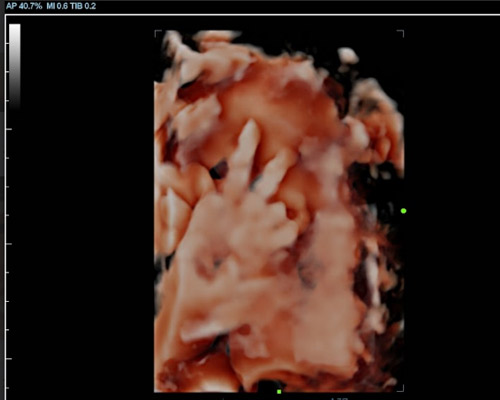

A 3D scan creates detailed still images showing your baby’s features, while a 4D baby scan allows you to see those images in motion. You may notice gentle movements, stretches, or even small expressions, which can make the experience feel much more real.

With a 4D baby ultrasound Huddersfield, this advanced imaging allows parents to see their baby in a way that feels closer to a photograph than a traditional scan.

Our Scans